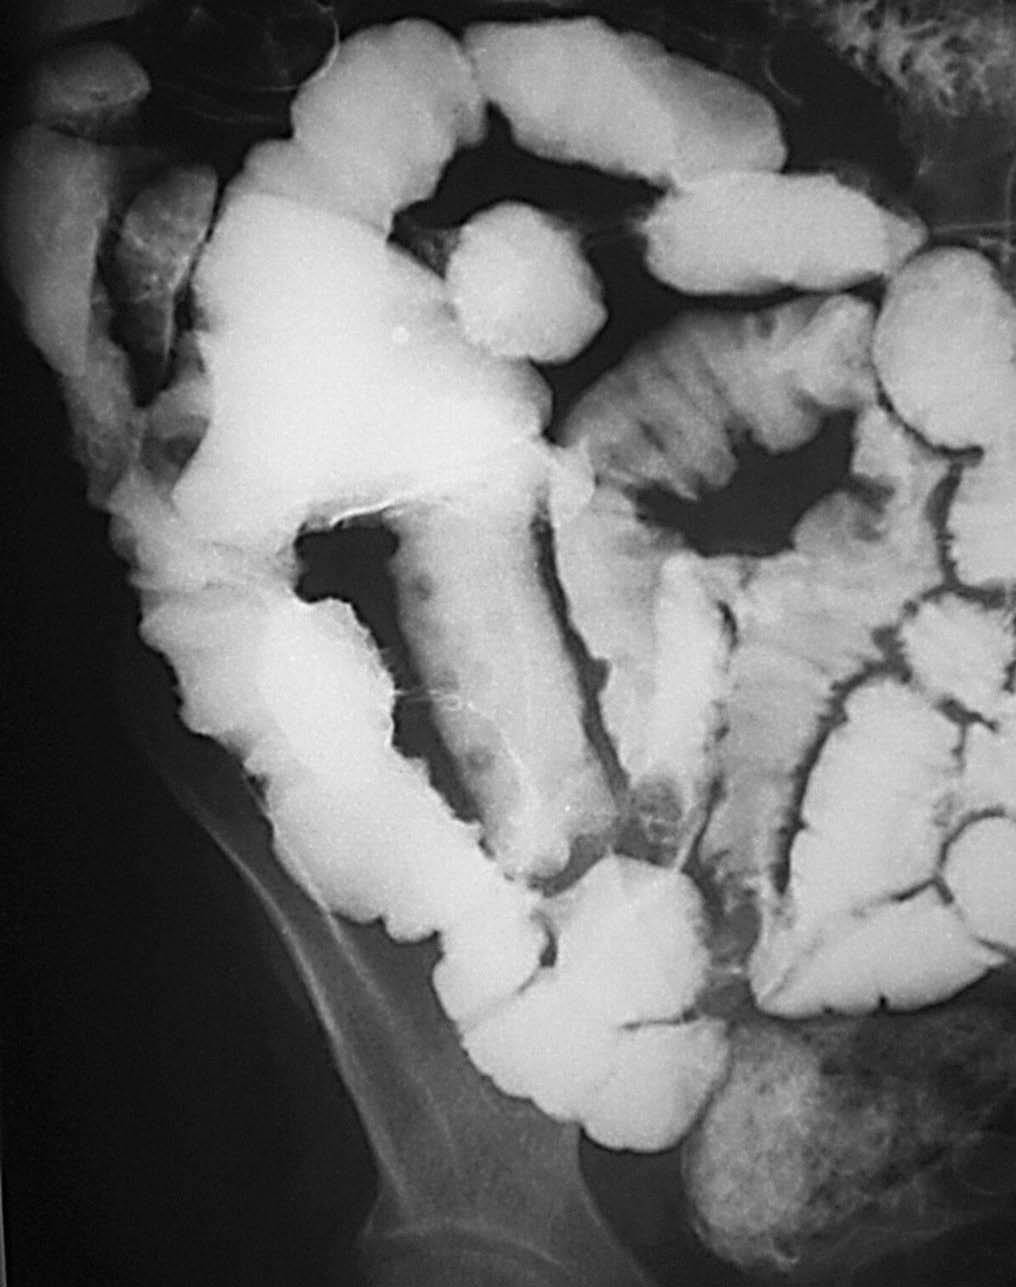

Así pues, los hallazgos radiológicos característicos en la fase inicial de la CU son el edema, la hiperemia, con pérdida de la radiolucencia normal de la mucosa (ya que resulta difícil definir de una manera nítida la imagen lineal de esta estructura). La presencia de secreciones abundantes en el interior de la luz del colon con un escaso contenido de moco justifica que el bario llegue casi a flocular, de ahí ese aspecto granular tan característico y la falta de haustración en relación con la relajación de las tenias. Los microabscesos crípticos tienen un aspecto moteado característico y su evolución normal son las ulceraciones en "T" o en "botón de camisa" que el estudio de doble contraste pone en relieve (fig. 13). El aspecto de doble pared del marco cólico, que se define como en "vía de tren" está en relación también con la presencia de las úlceras en "T" o en "botón de camisa"20.

Fig. 13.--Colitis ulcerosa. (A) Microabscesos crípticos en el estudio con doble contraste y su evolución normal a ulceraciones en "T" o en "botón de camisa". (B) El aspecto de doble pared del marco cólico se define como en "vía de tren".

Los hallazgos característicos de una fase más avanzada son la presencia de pseudopólipos con islotes de mucosa que se localizan entre las ulceraciones. En la TC esos pseudopólipos destacan de la mucosa de aspecto denudado como prominencias. Éstos pueden ser de todo tipo y condición: pseudopólipos lineales, pseudopólipos más abigarrados y grandes con un aspecto velloso.